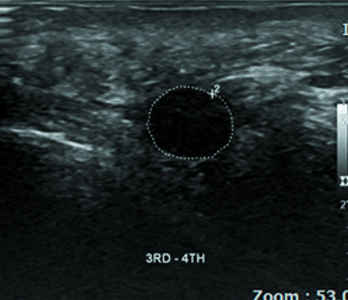

지간신경종

여성 지간신경종

Before

2020.10.14

After

2020.12.23

57세

2020.08.05

2020.12.02